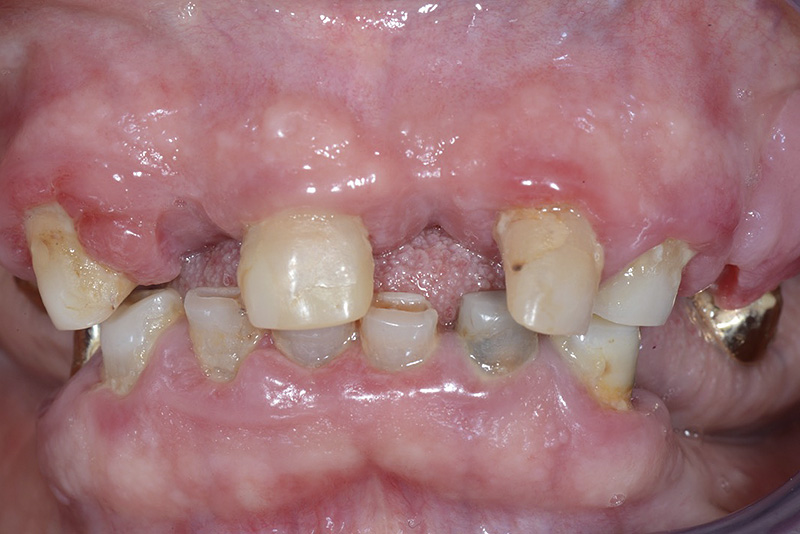

PREMESSA: in seguito all’estrazione dell’incisivo laterale superiore di destra, resasi necessaria per cause batteriche, si decide di affrontare il caso con il posizionamento di un impianto in sostituzione dell’elemento mancante dopo guarigione del sito infetto. Con tecniche rigenerative sia dei tessuti ossei mancanti a causa dell’infezione pregressa, sia dei tessuti gengivali che appaiono inizialmente troppo spostati in alto, si ripristina una corretta morfologia delle parabole (contorni) gengivali e delle papille interdentali (triangoli di gengiva tra due denti vicini).